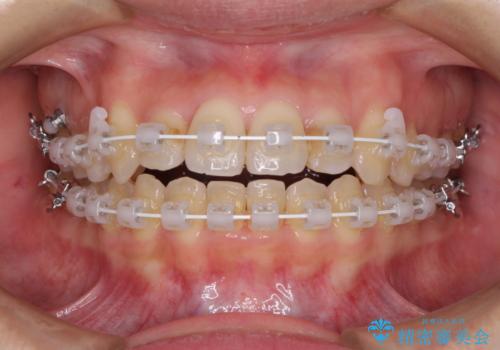

- 矯正装置

- 審美装置

より治療を速やかに行うため、上顎右側にアンカースクリューを使用し、目標としていた1年半ほどで治療を終えることができました。